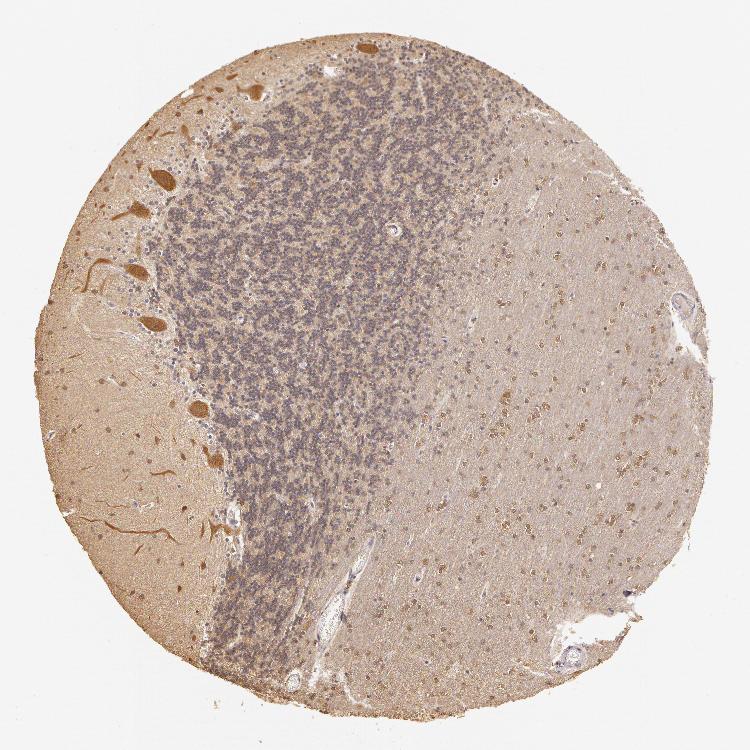

BRAIN CEREBELLUM Show tissue menu

CEREBELLUM - Expression summary

CEREBELLUM - Antibody stainingi

Antibody staining in the annotated cell types in the current human tissue is reported as not detected, low, medium, or high, based on conventional immunohistochemistry profiling in selected tissues. This score is based on the combination of the staining intensity and fraction of stained cells.

Each image is clickable and will lead to virtual microscopy that enables deeper exploration of all samples and also displays staining intensity scores, fraction scores and subcellular localization as well as patient and tissue information for each sample.

Antibody HPA000903Antibody CAB006244

Purkinje cells MediumHigh

Cells in granular layer Not detectedMedium

Cells in molecular layer LowHigh